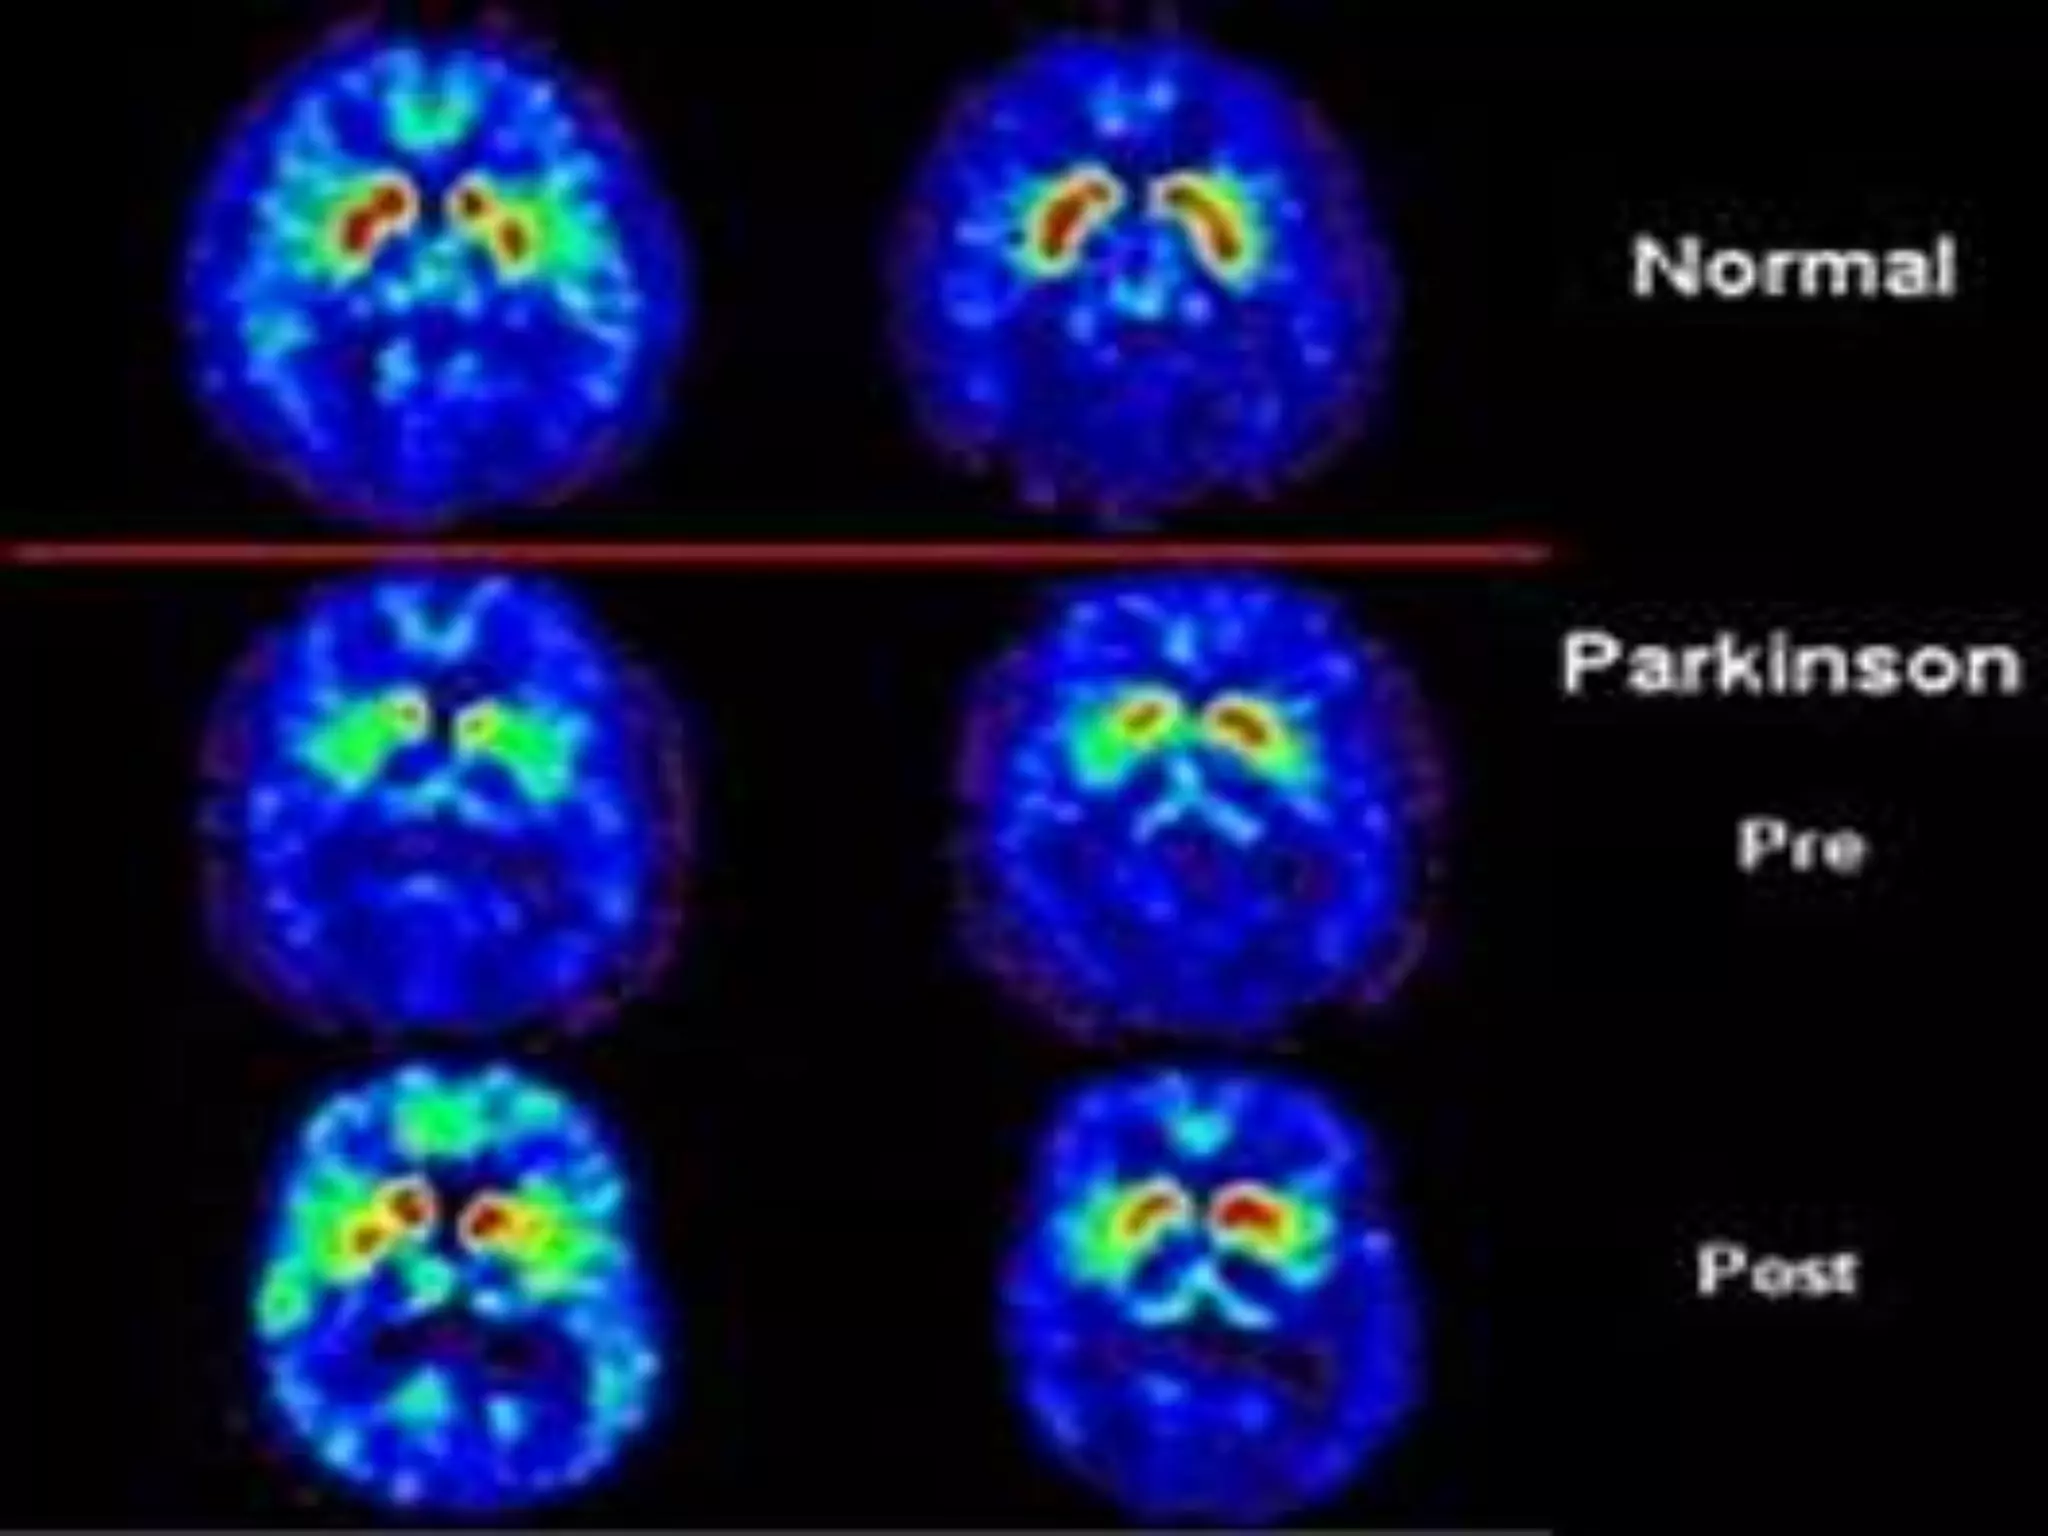

Differential diagnosis of parkinsonism using brain 18F-FP-CIT PET. Brain PET/CT images of 18F-FP-

CIT uptake at level of striatum demonstrate different DAT density in different conditions.

DAT density is decreased in PD patient (B), whereas DAT density is normal in healthy subject

(A) and in patients with drug-induced parkinsonism (C) and essential tremor (D).

Differential diagnosis ofparkinsonism using brain 18F-FP-CIT PET. Brain PET/CT images of 18F-FP- CIT uptake at level of striatum demonstrate different DAT density in different conditions. DAT density is decreased in PD patient (B), whereas DAT density is normal in healthy subject (A) and in patients with drug-induced parkinsonism (C) and essential tremor (D).